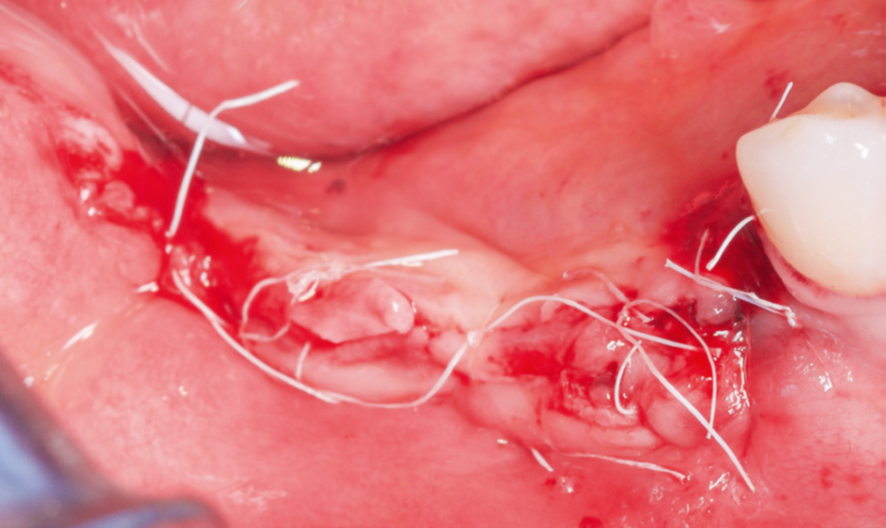

Após a maturação do tecido gengival, procedeu-se ao preparodo leito receptor com incisão e descolamento mucoperiosteal,liberando-se o tecido lingual por meio do alívio da tensão musculardo milo-hióideo (Figura 3) com o descolador de Molt (Supremo Instrumentais). Em seguida, prosseguiu-se com a coleta de osso autógeno do ramo mandibular (área próxima ao leito receptor, do mesmo lado, conforme Figura 4). As lâminas ósseas foram adaptadas e fixadas nas corticais vestibular e lingual com parafusos de titânio (Orth – Implacil Osstem / Figura 5), criando um compartimento do tipo caixa, preenchendo-se o seu interior com osso particulado autógeno (Figura 6). A sutura foi realizada com pontos em colchoeiro horizontal seguidos de pontos simples interrompidos (Figura 7). A cicatrização foi considerada satisfatória.

Figura 7 – Suturas com fio de PTFE (Microsuture) em colchoeiro horizontal e em pontos simples interrompidos.